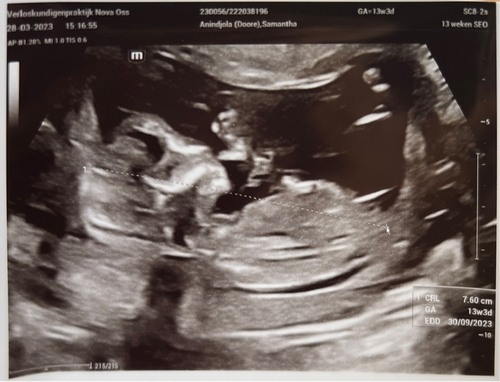

Vandaag de 13 weken echo, ben precies 14 weken. Zo spannend 🥰

Vandaag 13w echo gehad op precies 13 weken 🥰🥰 was heel beweeglijk en hele tijd aan het koprollen haha